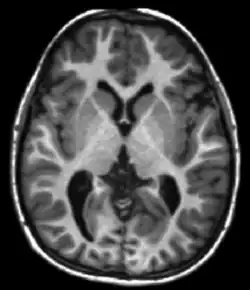

Neuroimaging

MRI is the investigative tool of choice for neurological cancers over CT, as it offers better visualization of the posterior cranial fossa, containing the brainstem and the cerebellum. The contrast provided between grey and white matter makes MRI the best choice for many conditions of the central nervous system, including demyelinating diseases, dementia, cerebrovascular disease, infectious diseases, Alzheimer's disease and epilepsy.[31][32][33] Since multiple images are taken milliseconds apart, it can show how the brain responds to different stimuli, enabling researchers to study both functional and structural brain abnormalities in psychological disorders.[34] MRI also is used in guided stereotactic surgery and radiosurgery for treatment of intracranial tumors, arteriovenous malformations, and other surgically treatable conditions using a device known as the N-localizer.[35][36][37] New tools that implement artificial intelligence in healthcare have demonstrated higher image quality and morphometric analysis in neuroimaging with the application of a denoising system.[38]